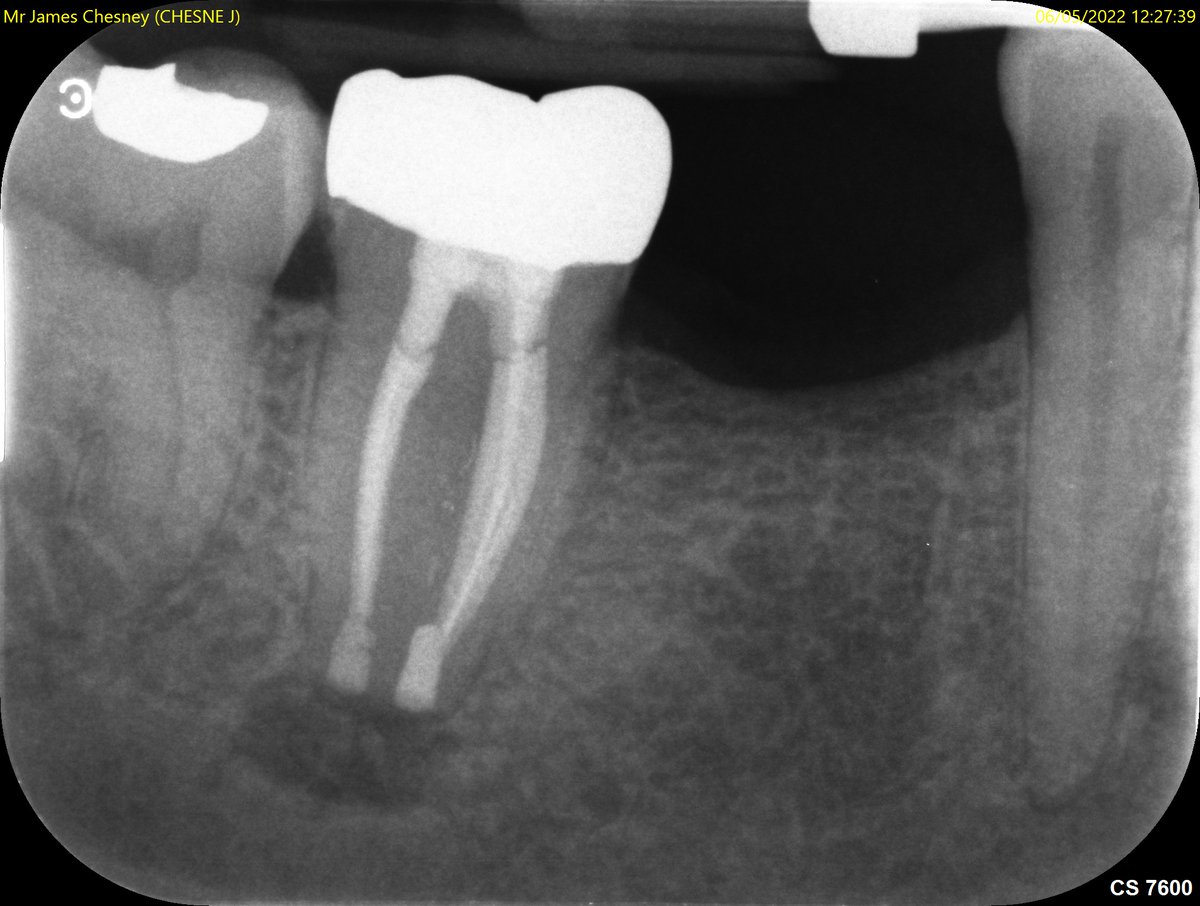

One year review of RCT UR6 with MB root resection doing well, symptom and sign free and beautifully restored by the referring dentist 😁 #savingteeth #endodontics youtu.be/pgO5aFGDeI4

One year review of RCT UR6 with MB root resection doing well, symptom and sign free and beautifully restored by the referring dentist 😁

#savingteeth #endodontics